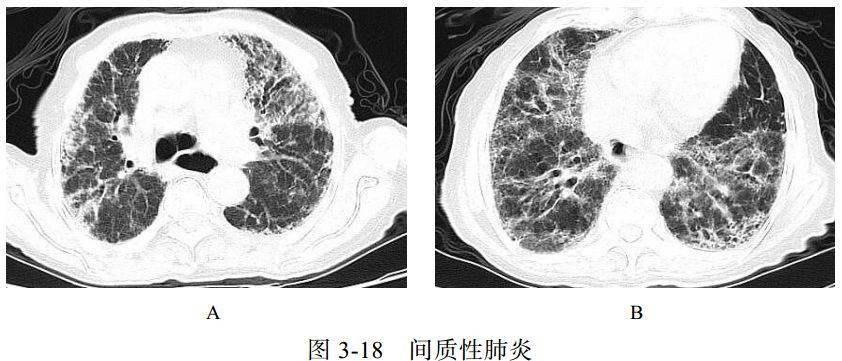

(四)间质性肺炎

肺间质纤维化性疾病包括一系列导致肺间质进行性纤维化的原发性或继发性结缔组织疾病,原发性主要为特发性肺间质纤维化,继发性主要包括系统性红斑狼疮、干燥综合征、类风湿关节炎等。特发性肺间质纤维化、系统性红斑狼疮、干燥综合征三种病变在影像学上表现相似,属于典型的“同影异病”,均表现为肺间质纤维化改变。细菌和病毒均可以引起间质性肺炎

影像学表现:两肺支气管血管束增多,网格状及小点状影,周围夹杂多发蜂窝状囊状影、肺气肿及牵拉性支气管扩张,相应胸膜下小叶间隔增厚(图 3-18)